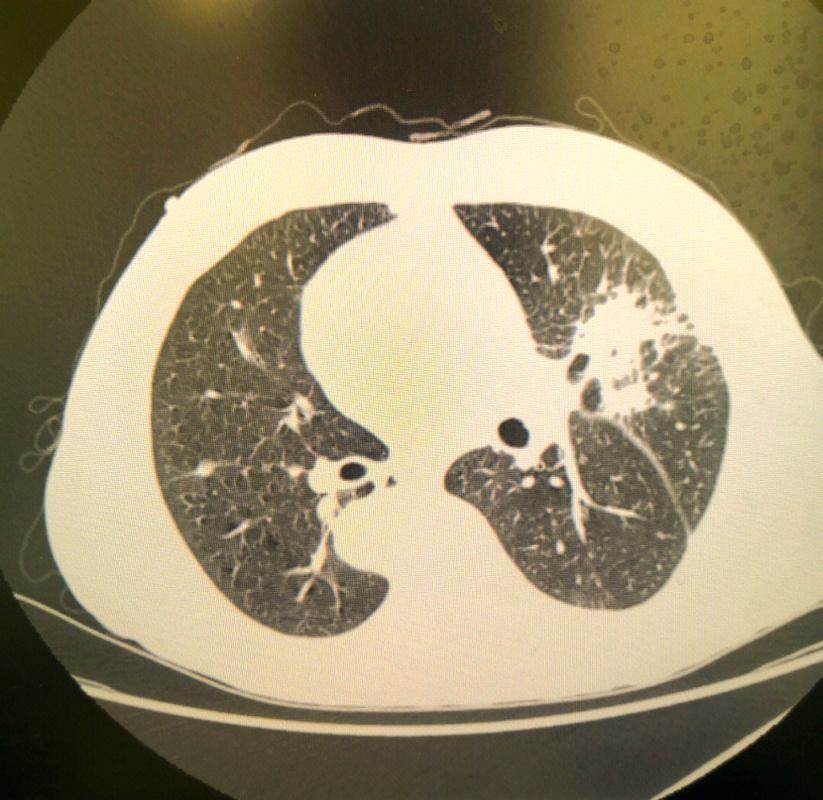

你一週抽菸幾根?10根?20根?還是像他,一週55次,平均每天抽8支,還不算應酬時的「敬菸+多點兒」。關鍵是,他從不咳嗽、不疼痛、精神還挺好。直到查出肺癌晚期,他還覺得「是不是拍錯了片」。

臨床上,我們發現越來越多40歲左右的患者,癌癥發現時已經是中晚期。他們不是不聰明,也不是不在意,而是被幾個「誤會」耽誤了。

誤會一:我不痛不癢,怎麼可能有大病?癌癥早期70%以上都沒有明顯癥狀